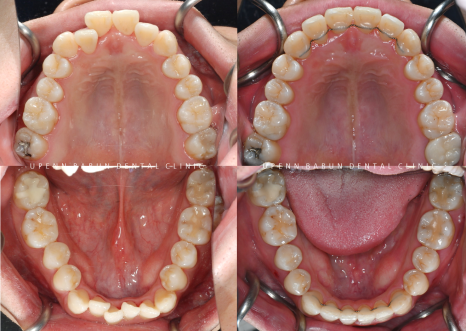

정중선이 맞아지고

정돈된 치열뿐만 아니라

반대교합이 있던 앞니와 어금니 모두

제위치를 찾아 올바른 교합관계가 되었습니다!

웃을때 이전보다 훨씬 세련되고 정돈된 이미지를 주는데요^^

입천장에 교정용 나사를 심어야 하는 악궁확장장치 없이

자체 악궁확장 기능이 있는 인비절라인으로

환자분의 고민이셨던

삐뚤빼뚤했던 치아를 개선하고

난이도 있는 부정교합을 해결해 드리니

환자분뿐만 아니라 저희도 기쁜 마음으로 마무리를 해드렸습니다! :)

발치 하지 않고 반대교합을 개선하고

치열을 가지런하게 마무리 해드렸습니다.

교정완료 후에는 안쪽에 유지장치를 제작해 마무리 해드렸습니다 :)